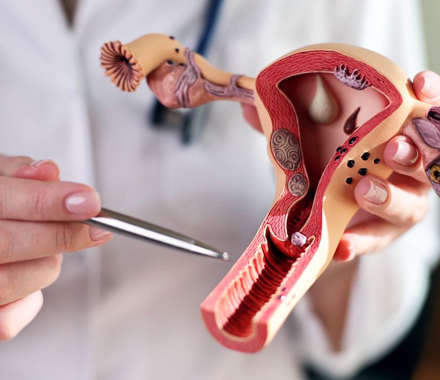

Abnormal Uterine Bleeding

Abnormal uterine bleeding is a condition in which a woman experiences.........

Ovarian Pathology

Ovarian pathology refers to conditions or diseases that affect the ovaries......

Uterine Pathology

Abnormal Uterine Bleeding

Ovarian Pathology

Uterine Pathology